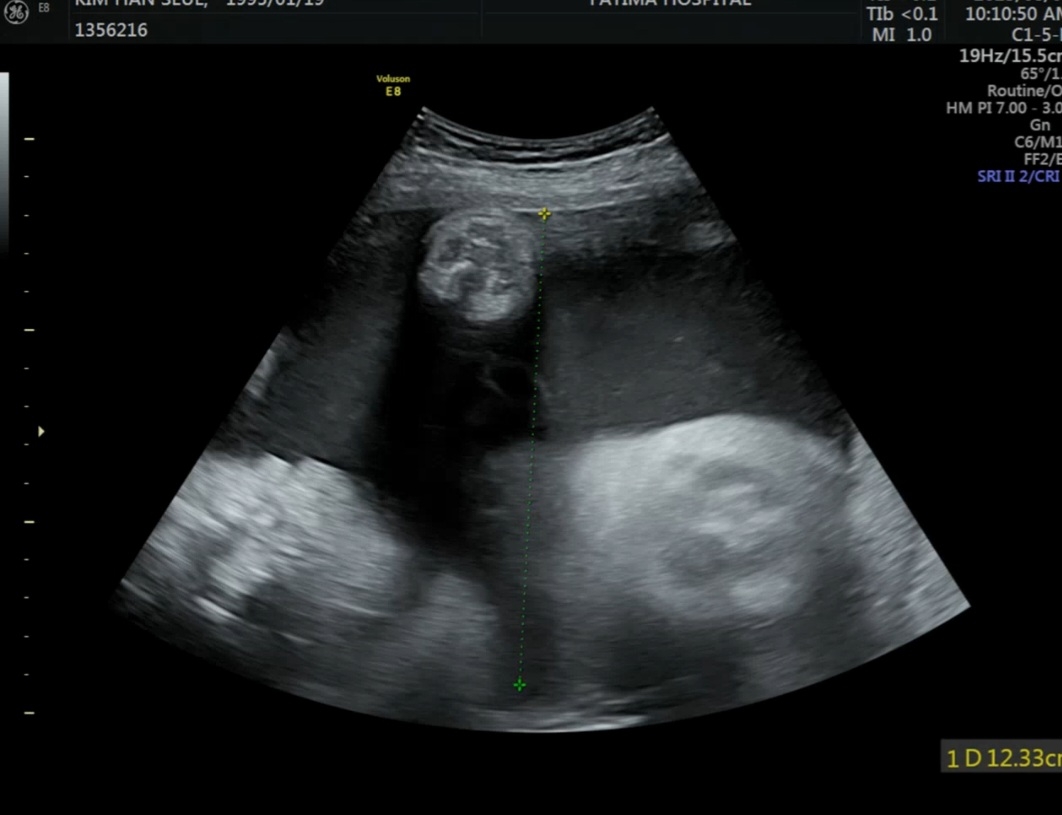

양수양이 많대요

35주 4일됐구요 양수양이 평균8-9? 10? 정도로 본다는데 저는 12정도 나와서 양수 양이 많다면서 제왕 한주 당기자고 하시더라구요 근데 정상기준이 어느정도인가요? 누구는 16이래도 괜찮다했다던데ㅠㅠㅠㅠ 걱정할정도는 아니죠???